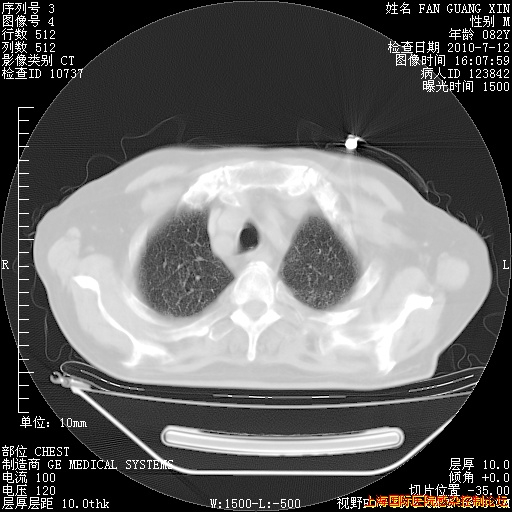

补发6月12日肺部CT肺窗

6月12日肺窗